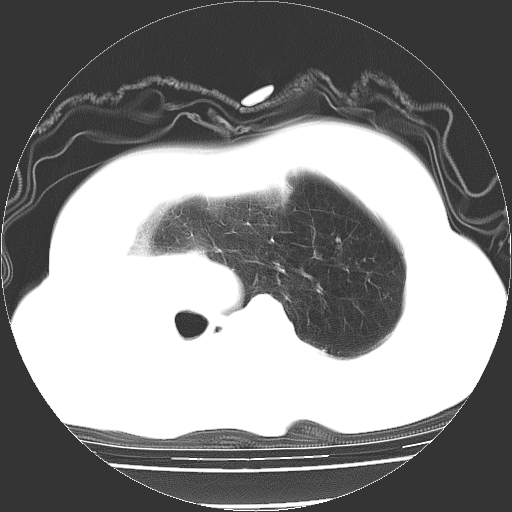

标题: CT23991:女,72岁,咳嗽、憋气一周。 [打印本页]

女,72岁,咳嗽、憋气一周,十年前曾患肺结核及胸膜结核。

1.右侧损毁肺伴胸膜钙化,2.左肺小结节灶,良性可能大,注意复查。3.肝脏左叶囊肿。4.先天性一侧肺不发育待出外(右侧胸廓无明显塌陷)。对比原片应该非常有帮助。

支持楼上,肝脏多发囊肿

右侧肺毁损,左肺代偿性肺气肿,纵隔疝。